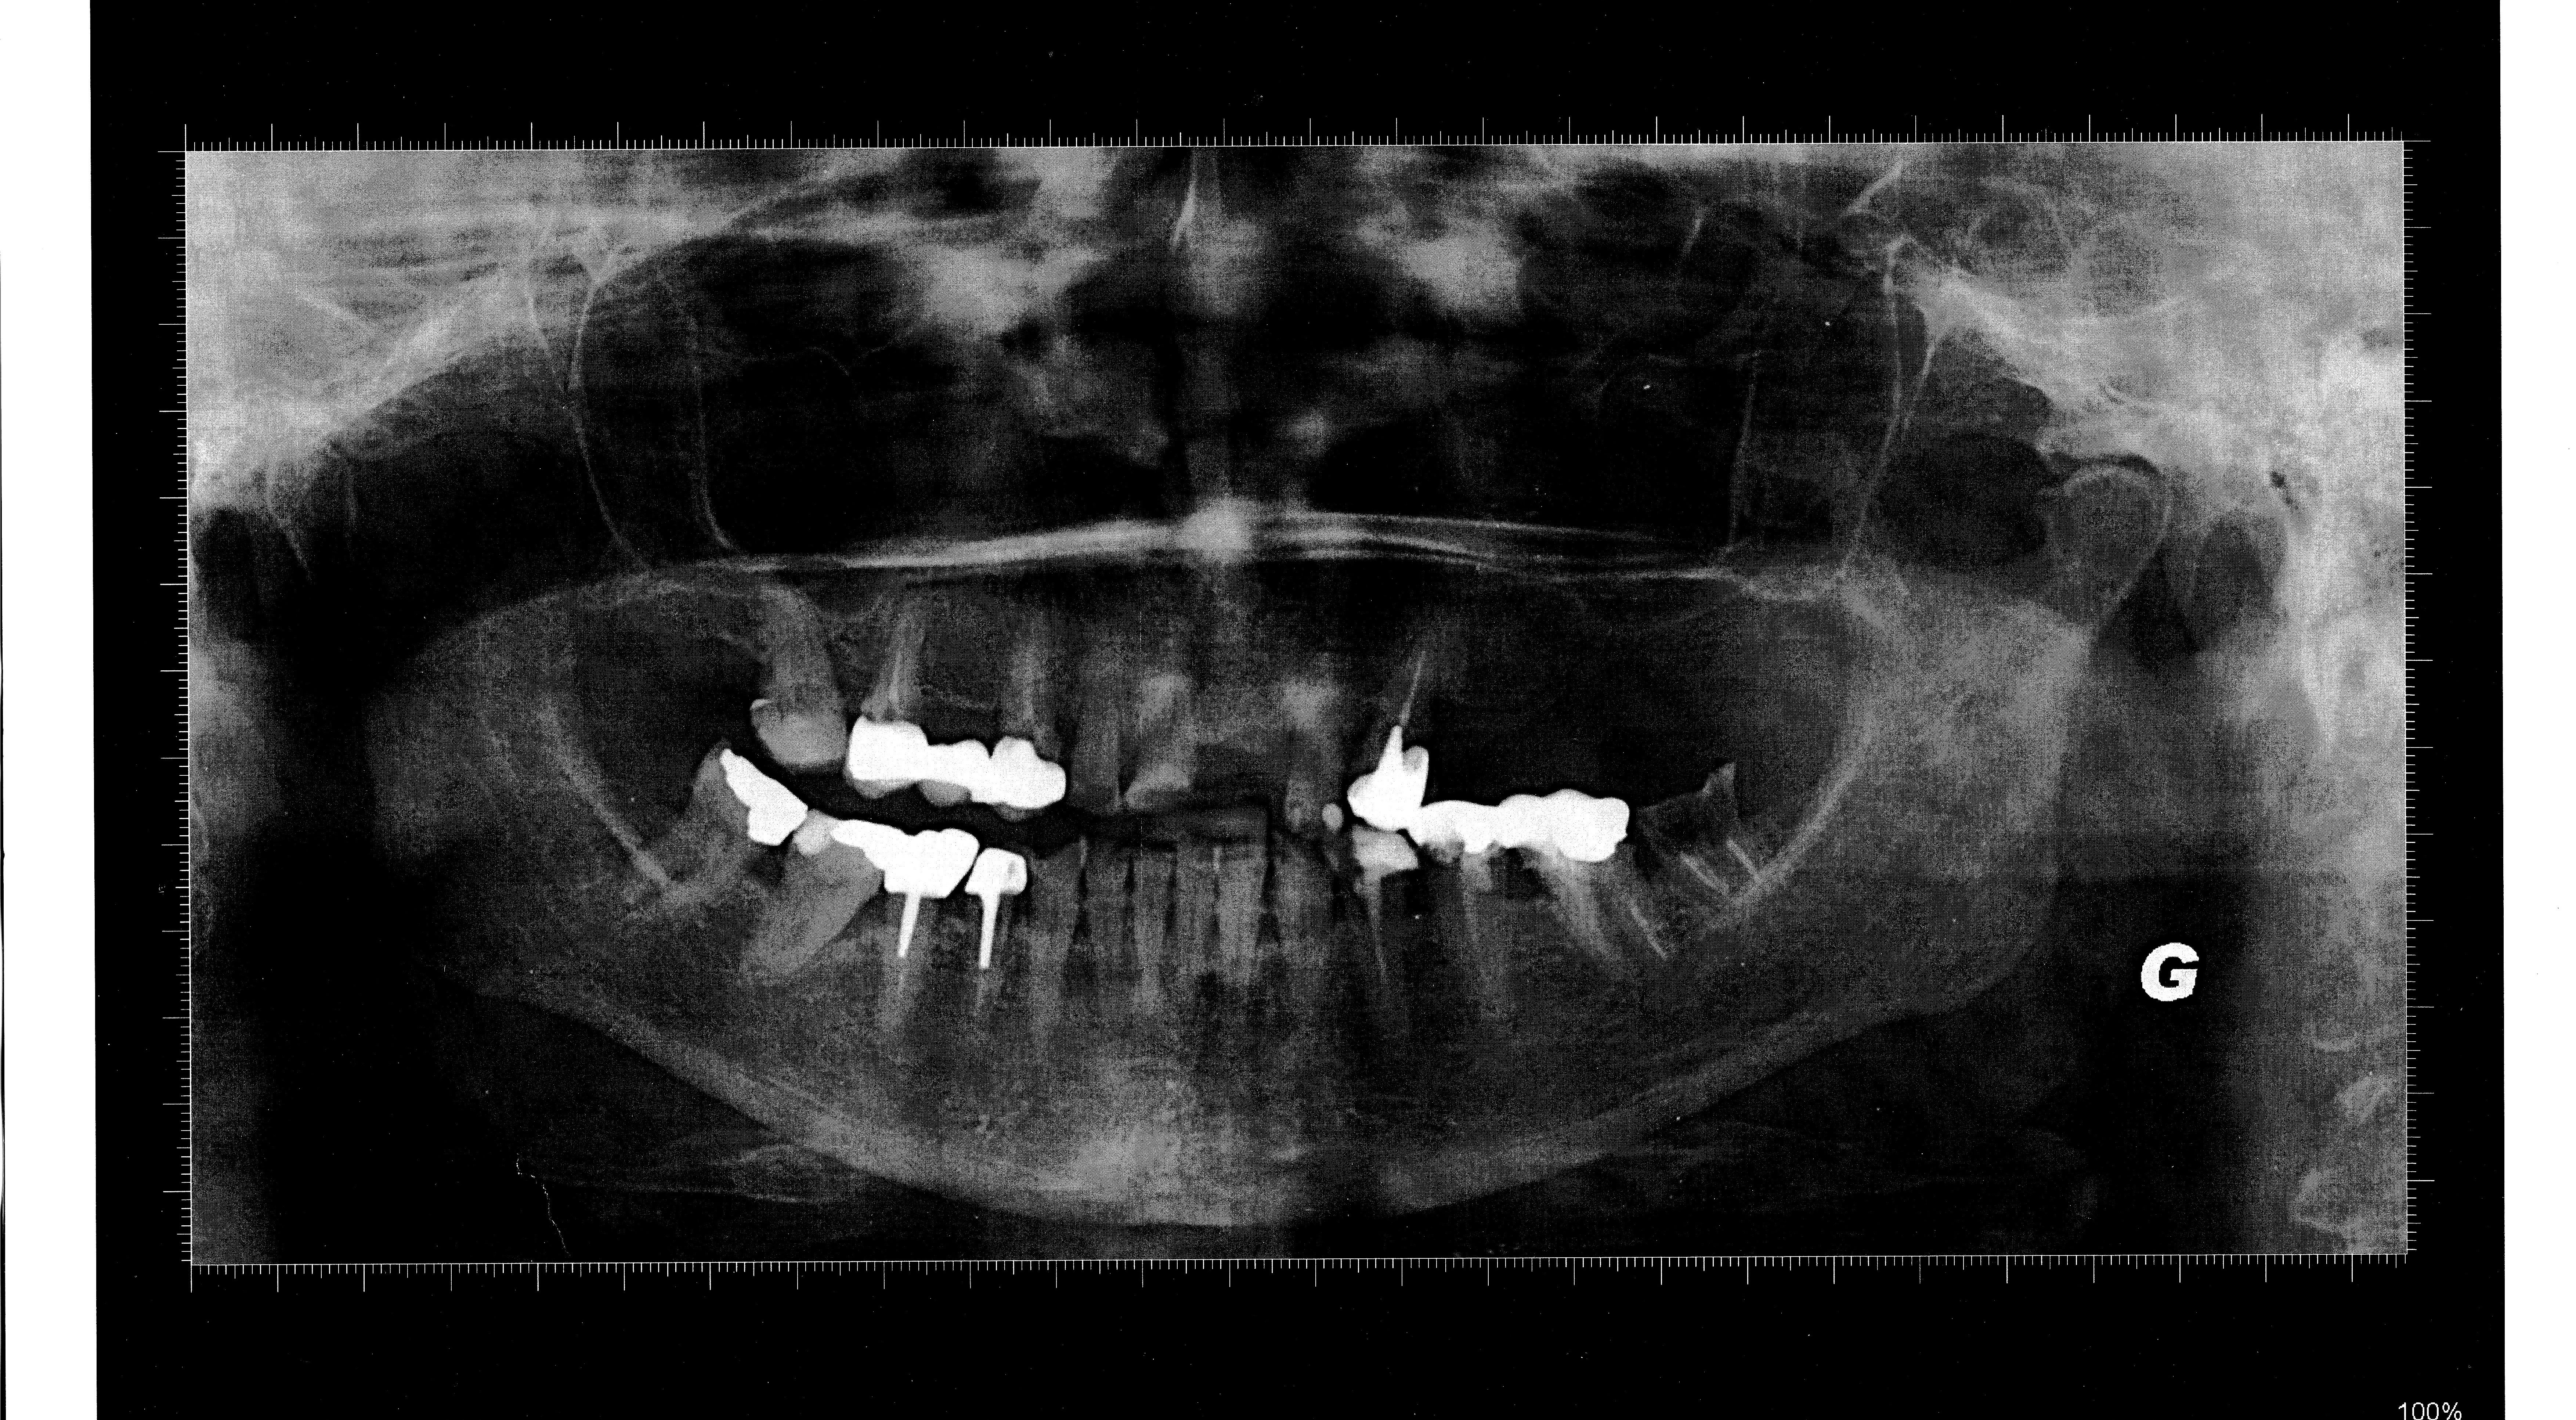

En bouche il y a un gros manque de DV, avec l’impression que tout a été reconstruit trop petit, trop bas, je ne comprend pas trop comment a été reconstruite la 23 qui semble beaucoup trop longue. Le stelite présente une particularité une selle mobile au niveau de la molaire S 2 pour "préserver la 23".

quand on voit cette ligne osseuse de plus grand contour , on se dit qu il y a eu une résorption osseuse horizontale du à un pb occluso paro .

mais si on y regarde mieux , on a l impression que cette crête est plus en avant que le surplomb des dents ant .

j ai comme l impression que c'était une classe 2 avec legere beance , qui par perte de calage post , que ce soit par perte des dents ou des protheses en sous occ ou meme la latero deviation de la canine ,aurait lingualé les incisives du bas et elles auraient reculé .

d où le recul des dents / à la crete osseuse .

ce qui voudrait dire que :

p'tre que la canine n etait pas trop grosse à l epoque , que le dentiste avait juste cherché à obtenir un contact palatin à l époque , et qu entre temps elle aurait eu une perte de dv par de multiples limages d équilibrations et par la vie tumultueuse .